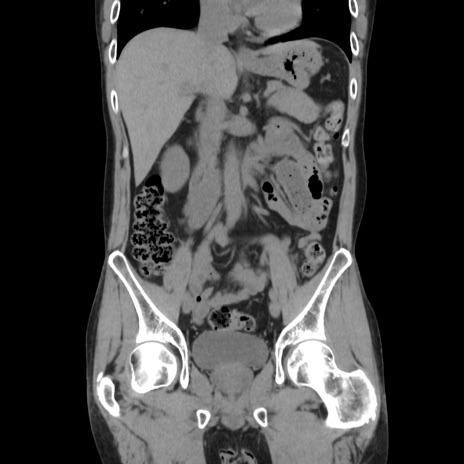

症例37(冠状断像)

【症例】40歳代 男性

【主訴】腹痛

【現病歴】4時間ほど前に電車に乗車中に臍部上より腹痛出現。徐々に増悪し起立困難となり、救急外来受診。生ものは数日食べていない。今朝お雑煮を食べた。

【身体所見】BT 36.8℃、BP 117/84mmHg、HR 91/min、SpO2 97%、苦悶様、腹部:臍上部広範囲圧痛あり、反跳痛±

【データ】WBC 8100、CRP 0.03